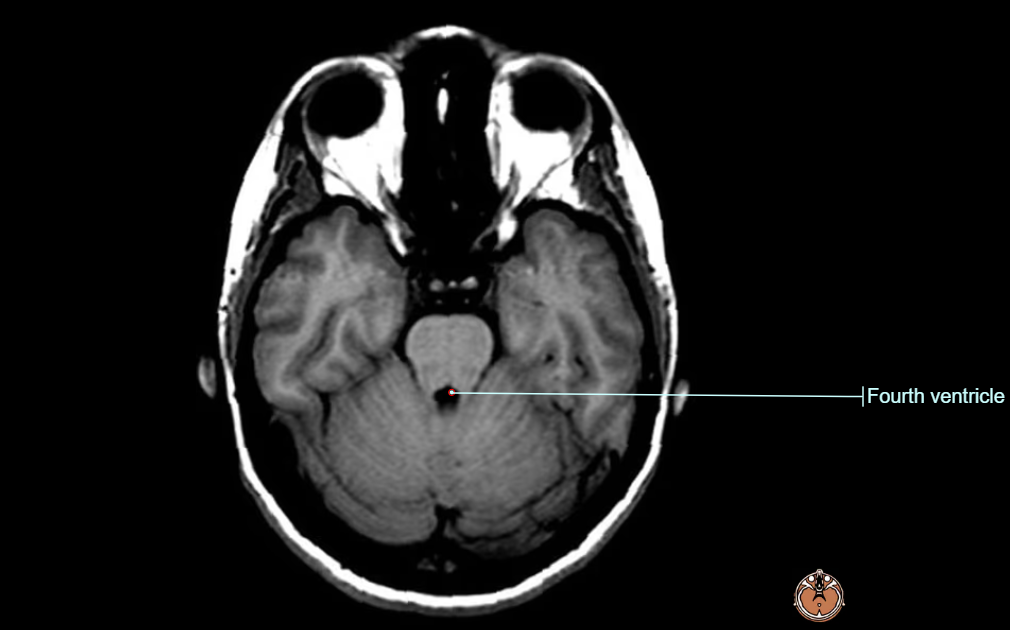

- 뇌 MRI(brain MRI) 영상은 T2 flair 및 brain DWI 영상에서 아래와 같은 영역에서 양측성 signal intensity의 증가 소견을 보이게 된다.

- tectal plate

- periaqueductal grey matter

- 흔히 병변이 확인되는 구조물 : the 3rd ventricle, aqueduct, fourth ventricle, dorsomedial thalamus, locus ceruleus, peri-aqueductal gray, ocular motor nuclei, vestibular nuclei, fornices, septal region, hippocampus, cerebral cortex 등에서 보이며, 주로는 대칭적으로 확인된다.